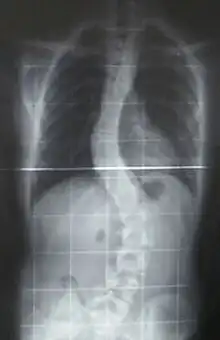

When scoliosis is suspected, weight-bearing, full-spine AP/coronal (front-back view) and lateral/sagittal (side view) X-rays are usually taken to assess the scoliosis curves and the kyphosis and lordosis, as these can also be affected in individuals with scoliosis. Full-length standing spine X-rays are the standard method for evaluating the severity and progression of the scoliosis, and whether it is congenital or idiopathic in nature. In growing individuals, serial radiographs are obtained at 3- to 12-month intervals to follow curve progression, and, in some instances, MRI investigation is warranted to look at the spinal cord.[35]

The standard method for assessing the curvature quantitatively is measuring the Cobb angle, which is the angle between two lines, drawn perpendicular to the upper endplate of the uppermost vertebra involved and the lower endplate of the lowest vertebra involved. For people with two curves, Cobb angles are followed for both curves. In some people, lateral-bending X-rays are obtained to assess the flexibility of the curves or the primary and compensatory curves.